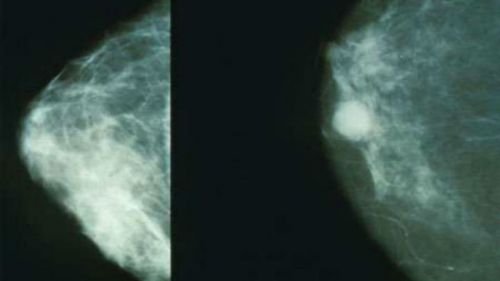

8. Маммография

После 40 лет необходимо ежегодно проходить маммографию.